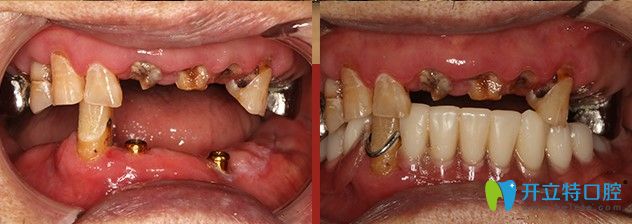

廣大口腔給韓重聲老人做種植牙的前后對比圖

顧客姓名:韓重聲/100歲

顧客身份:“解放戰(zhàn)爭、抗美援朝戰(zhàn)爭”功勛老軍人

顧客癥狀:上頜存牙較多,下頜僅剩五顆牙齒,四顆均有炎癥

治療方案:“高齡精準種”,即刻負重

主治醫(yī)生:侯國鎮(zhèn)主任

一生辛勞,誰都想安享晚年,老有口福。為種一口好牙,韓重聲老人早早來到了“高齡精準種”發(fā)布會現(xiàn)場。發(fā)布會結(jié)束后,老人來到了精準種植中心,韓老剛來到廣大口腔想要做種植的時候,口腔狀況并不樂觀。

術(shù)后CT片顯示,韓老口內(nèi)的種植體植入非常周正、位置和導板設(shè)計完全吻合,手術(shù)非常成功。王明霞醫(yī)生正在給韓老佩戴牙冠修復體。